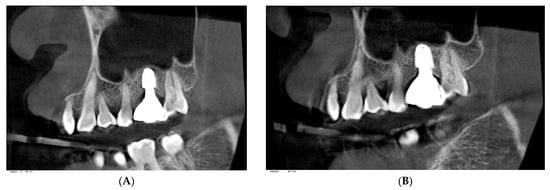

Prosthetic Management of Peri-Implant Mucositis via CRD Optimization: A Split-Mouth Case Report

Background: Subcrestally placed implants (SPIs) present advantages for bone preservation and soft tissue support but pose challenges in maintaining peri-implant soft tissue health. This case explores the role of Crest to Restoration Distance (CRD) in the development and resolution of peri-implant mucositis. Case [...] Read more.

Background: Subcrestally placed implants (SPIs) present advantages for bone preservation and soft tissue support but pose challenges in maintaining peri-implant soft tissue health. This case explores the role of Crest to Restoration Distance (CRD) in the development and resolution of peri-implant mucositis. Case Presentation: A 57-year-old woman received two SPIs—one in the upper left and one in the lower right first molar region. Despite similar implant systems and prosthetic protocols, the upper left implant developed mucositis, characterized by bleeding on probing and discomfort, while the lower right implant remained stable. Three-dimensional analysis using cone-beam computed tomography (CBCT) revealed excessive CRD at the affected site. Results: After prosthodontic revision to reduce the CRD, clinical signs of mucositis resolved, with probing depths reduced to less than 1 mm and no bleeding on probing. The control site remained healthy throughout the observation period. Practical Implications: This case highlights CRD as a modifiable prosthetic factor influencing soft tissue stability. A three-zone model—comprising the sulcus, transitional zone (TZ), and subcrestal zone (SZ)—is introduced to provide a biologically grounded framework for understanding soft tissue adaptation around SPIs. Full article